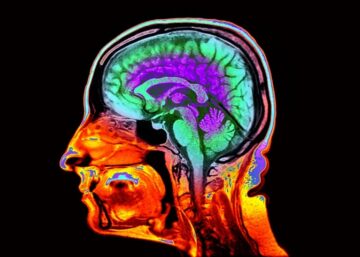

Telltale features visible in standard brain images can reveal how quickly a person is ageing, a study of more than 50,000 brain scans has shown1.

Pivotal features include the thickness of the cerebral cortex — a region that controls language and thinking — and the volume of grey matter that the cerebral cortex contains. These and other characteristics can predict the rate at which a person’s ability to think and remember will decline with age, as well as their risk of frailty, disease and death. Although it’s too soon to use the new results to assess people in the clinic, the test provides advantages over previously reported ageing ‘clocks’ — typically based on blood tests — that purport to measure how fast a person is ageing, says Madhi Moqri, a computational biologist who studies ageing at Harvard Medical School in Boston, Massachusetts.